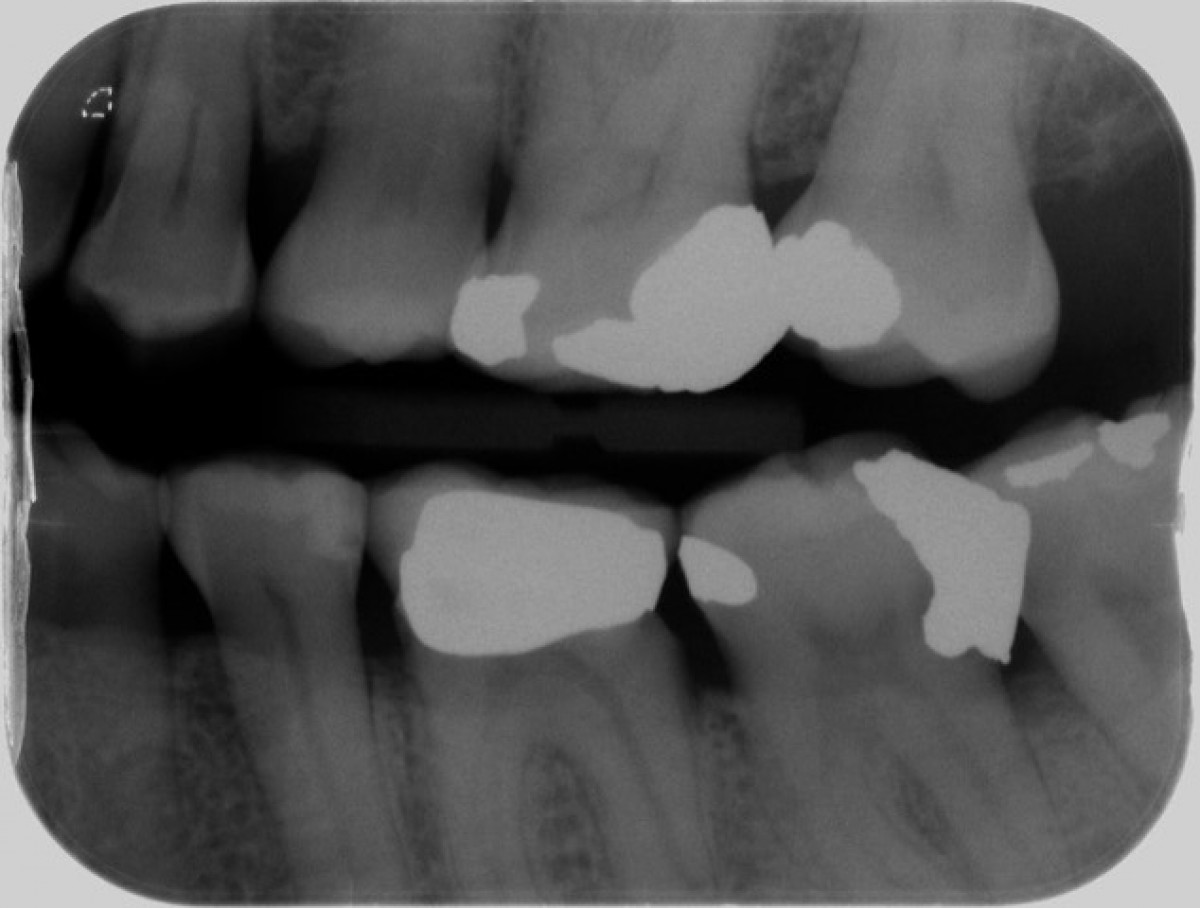

Facing a structurally-compromised teeth has always been a challenging procedure among dentists. Teeth with extensive deep caries, crown fracture and short clinical crown may end up with insufficient tooth tissue to support or retain a long lasting restoration. Additionally, deep subgingivally-prepared tooth margins have a higher chance of creating ill-fitted restorations that may violate supra-crestal attachment and compromise the periodontal health.

In these compromised clinical situations, several valid therapeutic approaches should be considered. Among them the Crown Lengthening Procedure (CLP) with osseous recontouring is a well-recognised option. This procedure contributes to the re-establishment of the supracrestal tissue and the exposition of a sufficient amount of tooth structure in order to support the future restoration. Currently, limited evidence is available in assessing the long-term outcomes of teeth preservation after CLP, thus making it difficult to take a decision whether to extract or preserve a compromised element.

A recently published retrospective study conducted by Dr. Ashnagar and his team in the Department of Periodontics and Oral Medicine at the University of Michigan, attempted to determine the long-term overall survival rate of structurally-compromised teeth that underwent crown lengthening procedure and restorative treatment. In this research work a thorough screening of all CLP-treated teeth in the Univeristy’s School of Dentistry was carried out between the year 1990 to 2015 for assessment and possible inclusion.

A total of 766 coded charts were initially collected. After careful evaluation of exclusion criteria, a total number of 414 teeth were included.